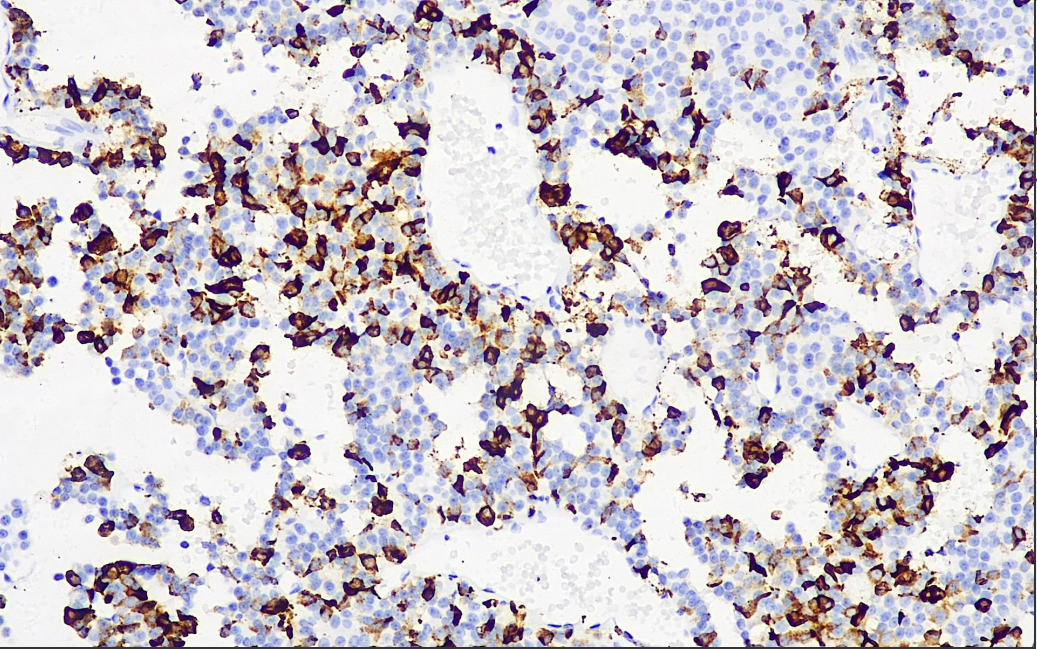

Positive control: Pituitary gland

ACTH is a hormone secreted by anterior pituitary cells. This antibody reacts with human ACTH and also cross-reacts with ACTH from a variety of mammals. It can be used to functionally classify pituitary adenomas, and can be used in studies to differentiate between primary and metastatic pituitary tumors. Some neuroendocrine tumors, such as pheochromocytoma, may also show a positive reaction.

ACTH Antibody Reagent binds specifically to ACTH molecular antigen. Immunohistochemistry kits containing ACTH Antibody Reagent are suitable for classification of the functionality of pituitary adenomas as well as for precise diagnosis of primary and metastatic pituitary tumors.